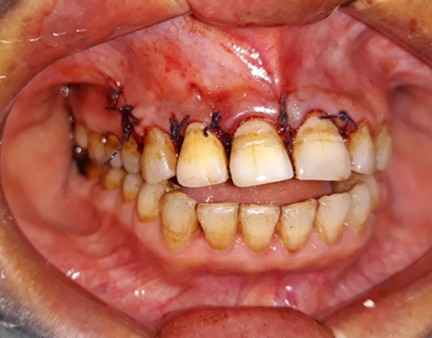

Radicular (periapical cysts) are the inflammatory type of odontogenic cysts associated with the root of non-vital teeth, typically asymptomatic. Radiographically, they appear as oval or pear-shaped unilocular radiolucency in the periapical region. Cyst development is the final stage of the inflammatory process after a periapical infection; hence, it often occurs later in life. Radicular cysts in the maxilla can occasionally spread across the maxillary sinus. The treatment modalities include endodontic treatment, enucleation with primary closure, and removal of the problematic tooth. Hence, the present study describes a successful case of endodontic treatment and surgical enucleation followed by placement of demineralised-freeze dried bone allograft (DFDBA) and platelet-rich-fibrin (PRF).